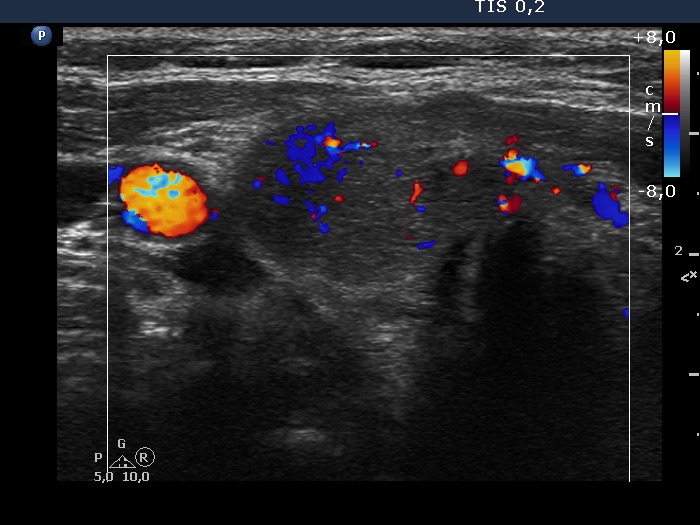

First examination (first, third and fifth rows of images):

Ultrasonography. The thyroid was echonormal and contained multiple inhomogeneous, partly blurred hypoechogenic and moderately hypoechogenic discrete lesions. Multiple lymph nodes were found on both sides of the neck.